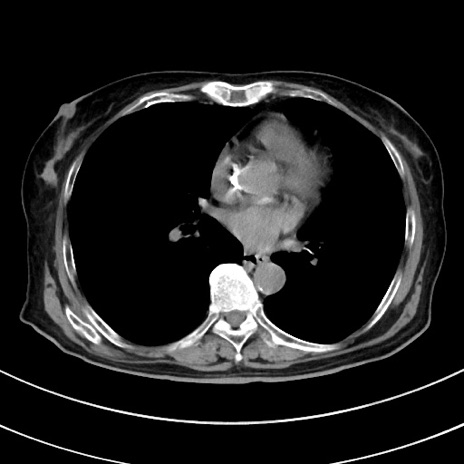

冠状断像

【症例】70歳代 女性

【主訴】心窩部痛

【現病歴】延髄病変の精査・加療にて神経内科入院中。本日より心窩部痛あり。

【既往歴】虫垂炎

【身体所見】右下腹部を中心に圧痛と反跳痛あり。

【データ】WBC 10900、CRP 0.02